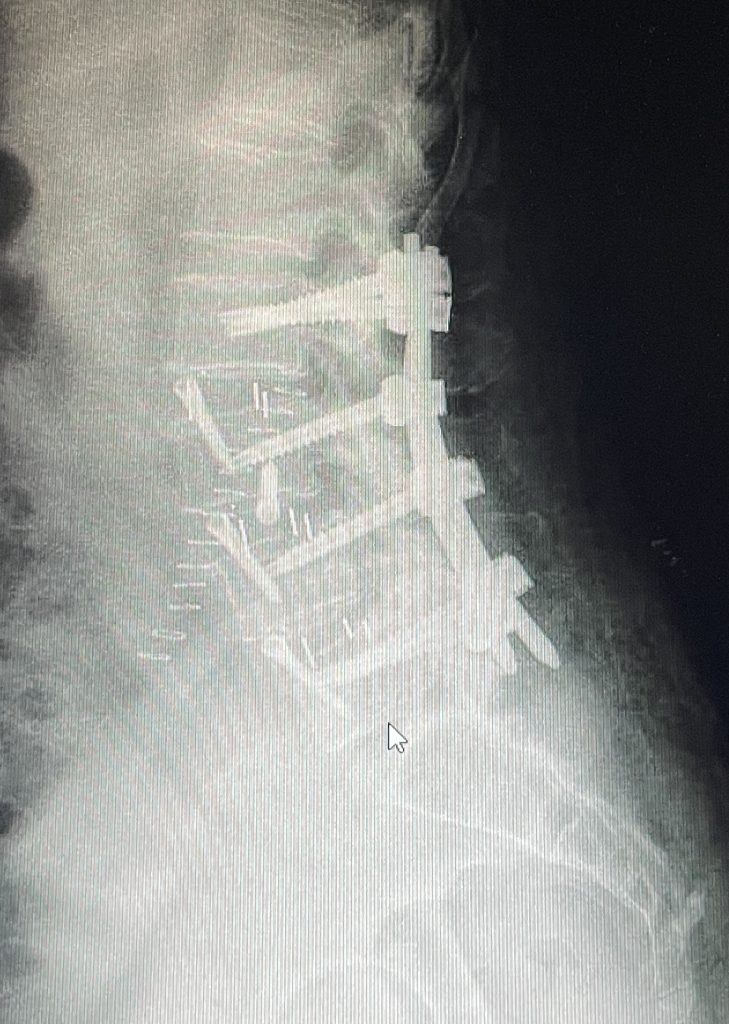

La artrodesis lumbar, convencional o mediante técnicas mínimamente invasivas, es la técnica estándar para solucionar los problemas de degeneración discal e inestabilidad en la columna lumbar. Consiste en fijar y fusionar vertebras entre sí, tras liberar las estructuras nerviosas atrapadas, anulando de este modo la movilidad anormal del segmento discal degenerado.

La artrodesis lumbar esta indicada en pacientes con degeneración dolorosa avanzada del disco intervertebral (discopatíadegenerativa lumbar), desplazamiento de una vértebra respecto a otra (espondilolistesis), inestabilidad de un disco intervertebral (hipermovilidad), desviaciones y deformidades de la columna (escoliosis o cifosis) y en casos de fracturas que requieran la estabilización de la columna.

Existen múltiples técnicas para conseguir la fusión de la columna lumbar. La artrodesis posterior instrumentada es la técnica más habitual. Consiste en colocar tornillos de fijación en las vértebras, y un implante a nivel del disco (caja intervertebral), lo que permite liberar nervios en el canal espinal y reconstruir la columna de un modo muy efectivo. La técnica habitual se denomina TLIF (transforaminal lumbar interbody fusion). Esta técnica también puede realizarse de forma mínimamente invasiva.